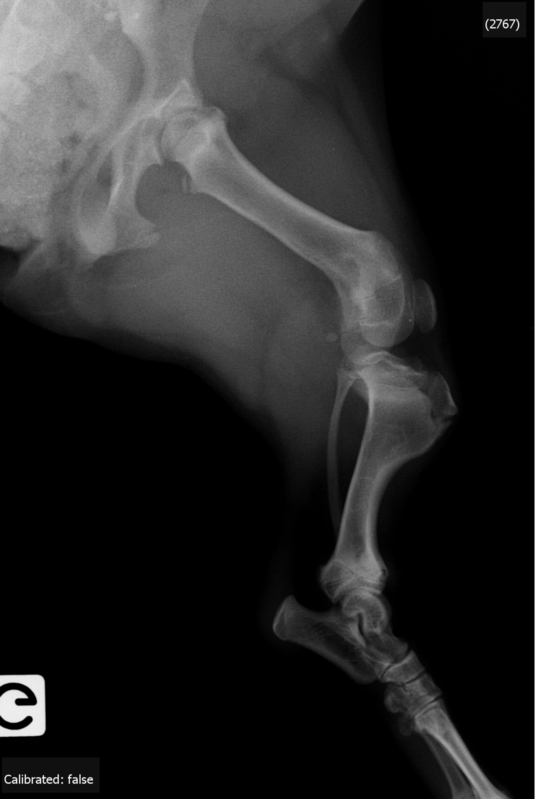

CAS CLINIQUE 1 : « FICELLE » est une femelle teckel de 6 mois qui présente une déformation bilatérale des tibias («pes varus» congénital)…

RADIOLOGIE :

INTERPRETATION :

- bascule en varus de la métaphyse tibiale distale bilatérale de 30° minimum

- pas de signes objectifs d’une fermeture partielle asymétrique du cartilage de croissance distal du tibia

- pas de signes évidents de rotation interne

- longueur tibiale identique sur les deux membres postérieurs

- raccourcissement longueur corticale médiale / latérale bilatérale

CONCLUSION :

- pes varus bilatéral sans antécédents de traumatisme

- origine génétique suspectée